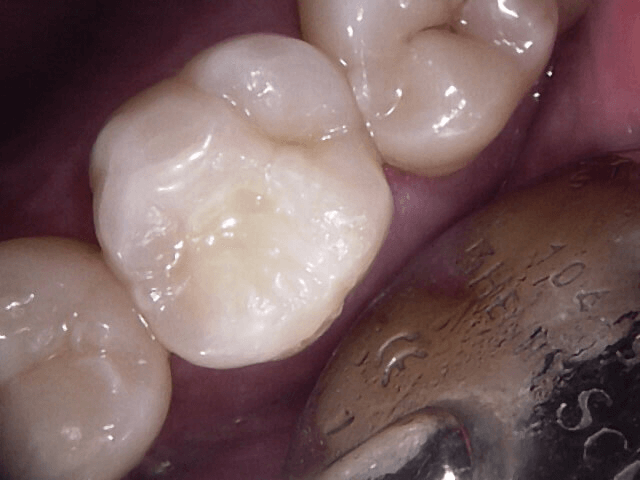

Dental Sealants and Painless Preventative Fillings in Guelph

Sometimes despite proper brushing and flossing, there can still be a chance of developing tooth decay in and around the grooves of your teeth. The tiny fissures and pits on the chewing surfaces and corner cusps of your molar and premolar teeth become susceptible to plaque and tartar build up that may be leading to tooth decay. Dental sealants can be an effective and long-lasting approach to preventing tooth decay and cavities where things appear to be susceptible.

In cases where it is clear surface decay is present in your hard-shell layers of your teeth, and brushing isn’t likely to stop the inevitable destruction of additional sound tooth structure, we can provide a quick, safe and pain-free solution. Preventative white fillings are typically placed painlessly and without the need for freezing. They very quickly restore a tooth to it’s more cleansable self.